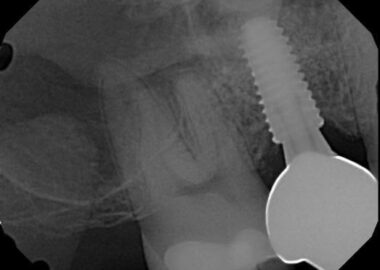

The patient was referred by Dr. S for assistance in retrieving an abutment screw in a Hiossen 4.5 implant in the #3 site. Evidently, the crown was delivered and within a very short time, less than 24 hours, the crown was “loose” so the long journey with this implant began. Multiple prior attempts were made to retrieve this screw by several dentists all of which were unsuccessful. The net result was the drive geometry in the screw head was rounded and the patient was referred here to clear the implant. The normal retrieval protocol was discussed with Eli and his mom and the head of the screw was accessed confirming the loss of geometry in the screw head. Quickly it became apparent a routine slot in the screw head and retrieval would not be sufficient to mobilize this screw. So, the head of the screw was removed along with the crown exposing the head of the implant and the remaining screw shaft which was up well above the implant threads. With this advantage, two small opposing flats were placed into the screw shaft and a custom driver was slotted to fit the existing screw geometry. Twice this was done and both times the applied torque was sufficient to fracture the screw shaft just below the slot. It became apparent this screw was very resistant to retrieval and a total drill out might very well be necessary. At this time, the reason for this event was totally unclear. The questions were why did the abutment become loose in such a short time period, yet the screw could not be retrieved?

The patient returned for a second appointment to center drill the screw and remove, if possible. If not, then a complete drill out would be indicated. Utilizing custom precision guidance with microscope tracking the screw was spot drilled, and then center drilled with effort to stay concentric on the fragment. The first attempt with the easy out screw extractor was not positive so the first two mm of the screw, which was above the implant threads, was enlarged to 1mm. The extractor was then re-engaged successfully, and the screw was delivered. The amount of torque required to achieve success was not measured but it was significant. Enough to split the screw shaft in the section above the implant threads. The implant was not damaged by any of the retrieval efforts so the prognosis going forward should not be altered.

Was it the incorrect screw? I measured the screw fragment on my 14” optical comparator and it measured to be a M2x.4 screw. Correct for this implant. That eliminates the possibility of an undersized screw, with a different thread pitch, cross threading more and more as it progresses into the implant threads. I don’t believe the abutment was seated cross hex and hence the reason for the early looseness, as there was no indication of hex damage on the abutment or in the implant. I also do not believe the correct screw was cross threaded which prevented total screw seating as there was no damage to the implant threads and the screw was delivered too deep into the implant not to see this. The only explanation I have is that the screw never really secured the abutment tightly even though the screw was torqued with the prescribed applied torque not being able to thread through an obstruction in the threads and establish preload on the screw. The abutment would have just walked out of the hex early after delivery. That would mean the screw threads hit something which prevented the head of the screw from engaging the screw head seat. If that was so, then that would explain why the screw could not be moved even though the abutment was loose with no preload on the screw. After removing the screw fragment, I was able to easily pass a tap through the implant threads, so nothing was found there. Possibly the obstruction was in the screw threads which then cleared with the screw fragment retrieval? I do know this was a very difficult retrieval bordering on a complete drill out, so something was preventing the normal rotation in the threads. If it wasn’t a parts misfit, then it must have been debris of some kind. I simply do not have a third possibility at this time.